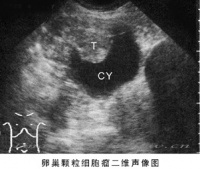

卵巢颗粒细胞瘤

为最常见的一种具有内分泌(以雌激素为主)功能的卵巢肿瘤。占全部卵巢肿瘤的1~2%。可发生于任何年龄,据上海医科大学等统计,平均发病年龄为52岁,60%在绝经期后,青春期前者<5%。图示右卵巢区囊实性肿块,囊壁附有乳头状实质性回声团块。T=肿块;CY=囊液。